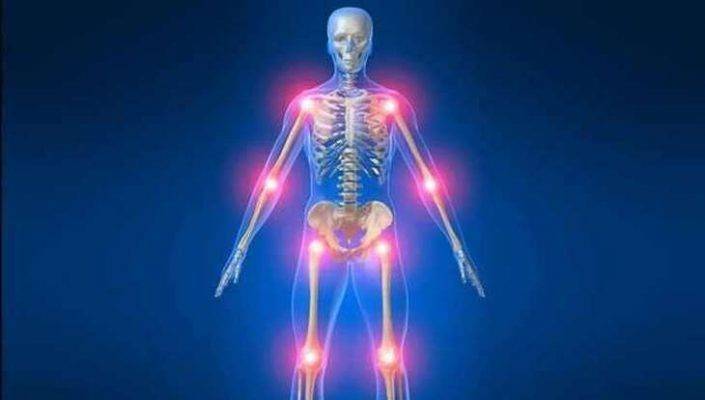

- Continuous and severe pain: If you experience continuous and severe pain in both shoulders for an extended period without improvement, it could be a sign of a serious issue. These symptoms may indicate shoulder joint inflammation, ligament tears, or another problem that requires proper medical treatment.

- Additional symptoms: If shoulder pain is accompanied by additional symptoms such as swelling, redness, and warmth in the shoulders, it may be indicative of inflammation or infection in the joints or surrounding tissues. In such cases, urgent action should be taken to receive the necessary treatment.

- Changes in sensory or motor function: If you notice changes in sensory or motor function in your shoulders, such as weakness or numbness in the upper limbs, it may indicate a neurological problem or a disorder in the muscles near the shoulder. In such cases, it is essential to consult a neurologist for a thorough examination and accurate diagnosis.

- Concurrent pain in other areas: If you are experiencing pain in other areas such as the chest, back, or arms in addition to your shoulders, this may be a sign of a heart or spinal issue. It is advisable to consult a doctor to assess these symptoms and determine the potential cause.

Left Shoulder Pain as a Warning Sign: Left shoulder pain with minimal exertion can indicate an issue with the coronary artery, which supplies blood to the heart muscle. Pain in the left shoulder may also be accompanied by chest or arm pain. Shoulder Pain and Heart Problems: Left shoulder pain with minimal exertion is considered a warning sign of coronary artery problems, which may suggest heart diseases. Shoulder pain can be due to coronary artery blockage, reducing blood flow to the heart muscle and causing pain. Medical Diagnosis: If you experience left shoulder pain with minimal exertion, you should visit a specialized doctor promptly. Medical diagnosis may require some tests, such as resting electrocardiogram (ECG), stress ECG, coronary angiography, and computed tomography angiography of the coronary artery. Early Diagnosis: Early diagnosis of heart problems and identifying important coronary artery blockage cases are essential to avoid serious complications. It is crucial to consult a doctor if you experience recurrent left shoulder pain, especially if it is accompanied by chest or arm pain and occurs with minimal exertion. Preventing Heart Diseases: Avoiding smoking, following a healthy diet, and regularly exercising may reduce the risk of heart diseases. It is also important to visit a doctor for regular heart check-ups and necessary tests for early detection of any issues.